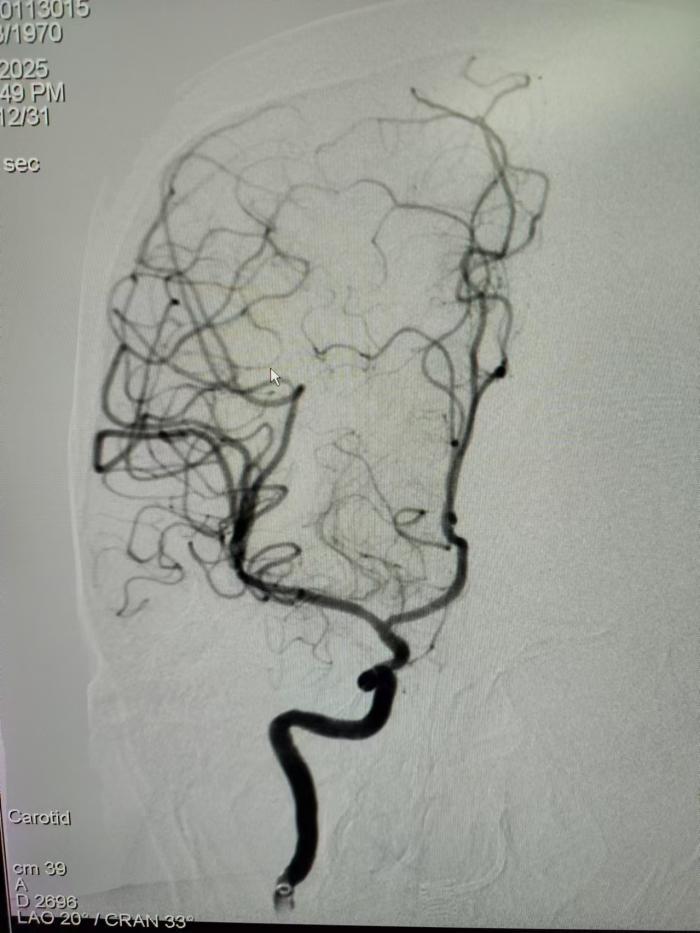

取栓前,血栓堵塞血管,血流减少,将导致脑组织缺血坏死

取栓后,血栓取出,血管血流恢复,不影响脑部功能,从而避免卒中后致残的发生。